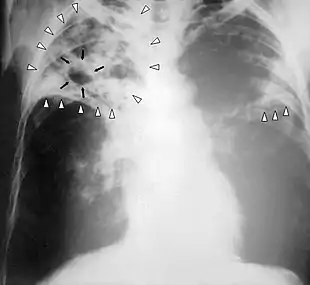

Chest X-ray of a person with advanced tuberculosis: Infection in both lungs is marked by white arrow-heads, and the formation of a cavity is marked by black arrows.